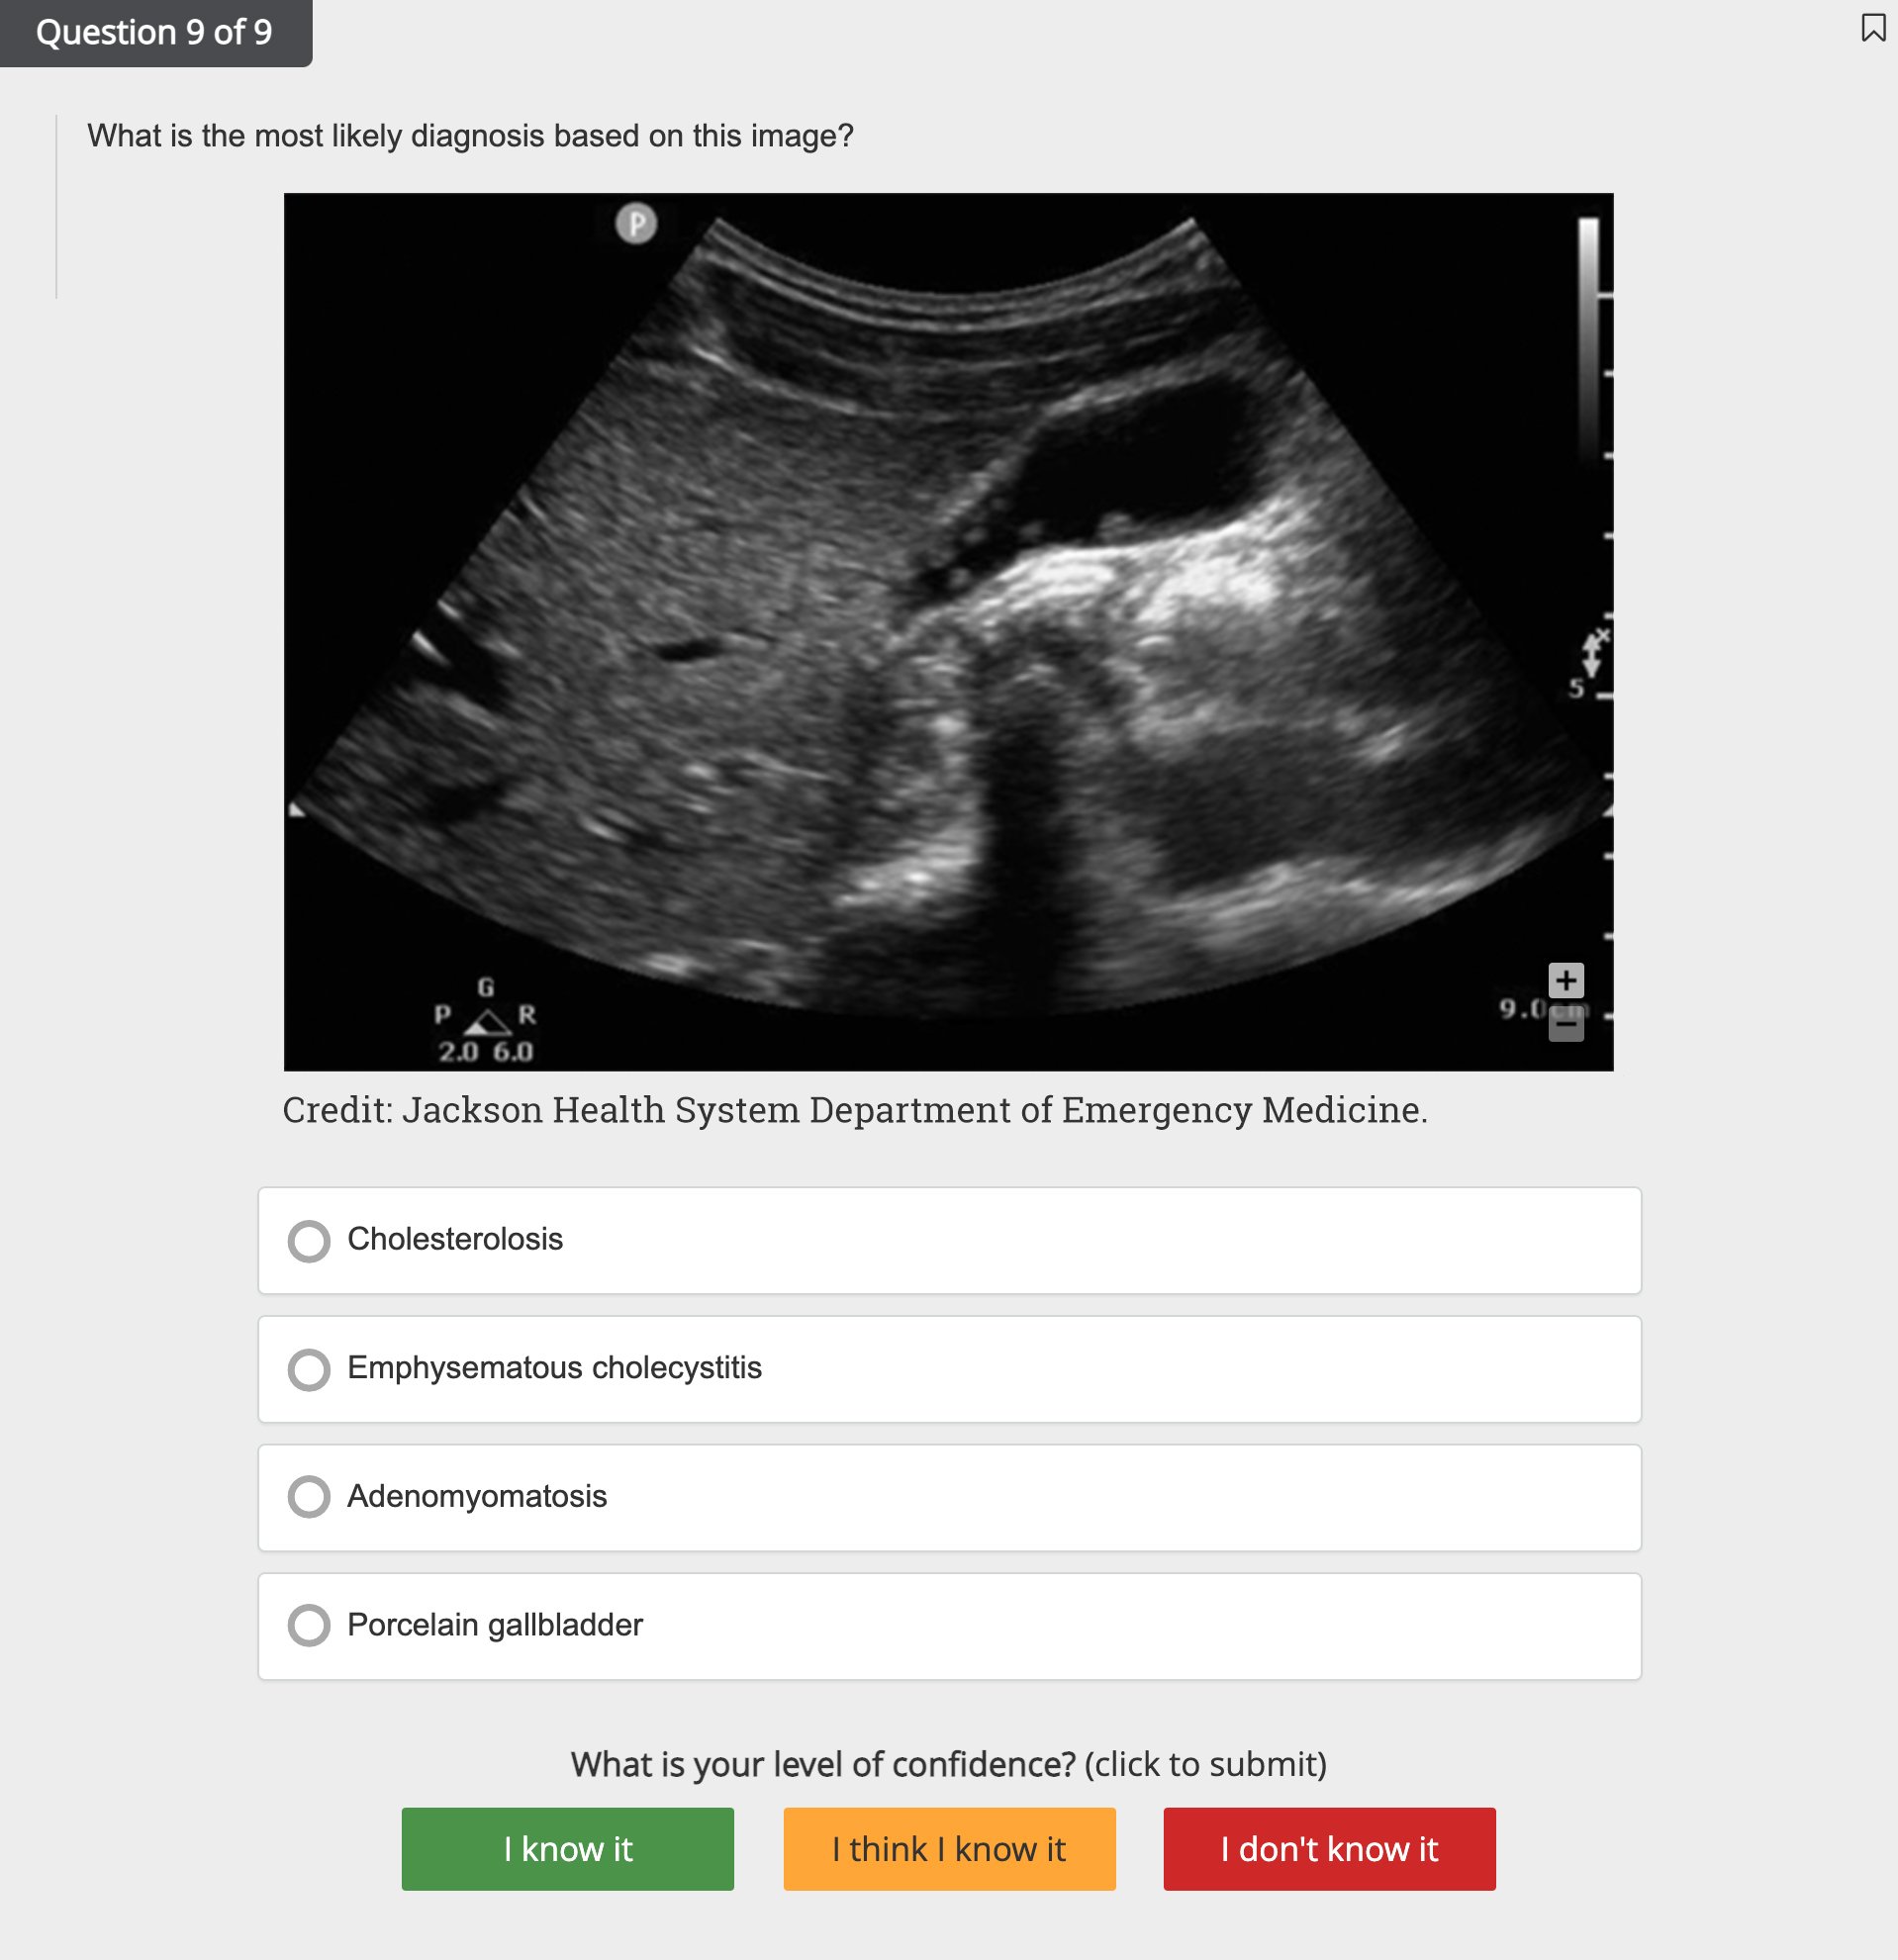

- Review numerous image- and video-based ultrasounds, along with quick study aid infographics

- Study relevant imagery and videos in tandem with answer explanations

- Explore the First Aid Kit library with nearly 300 ultrasound images, infographics, and videos